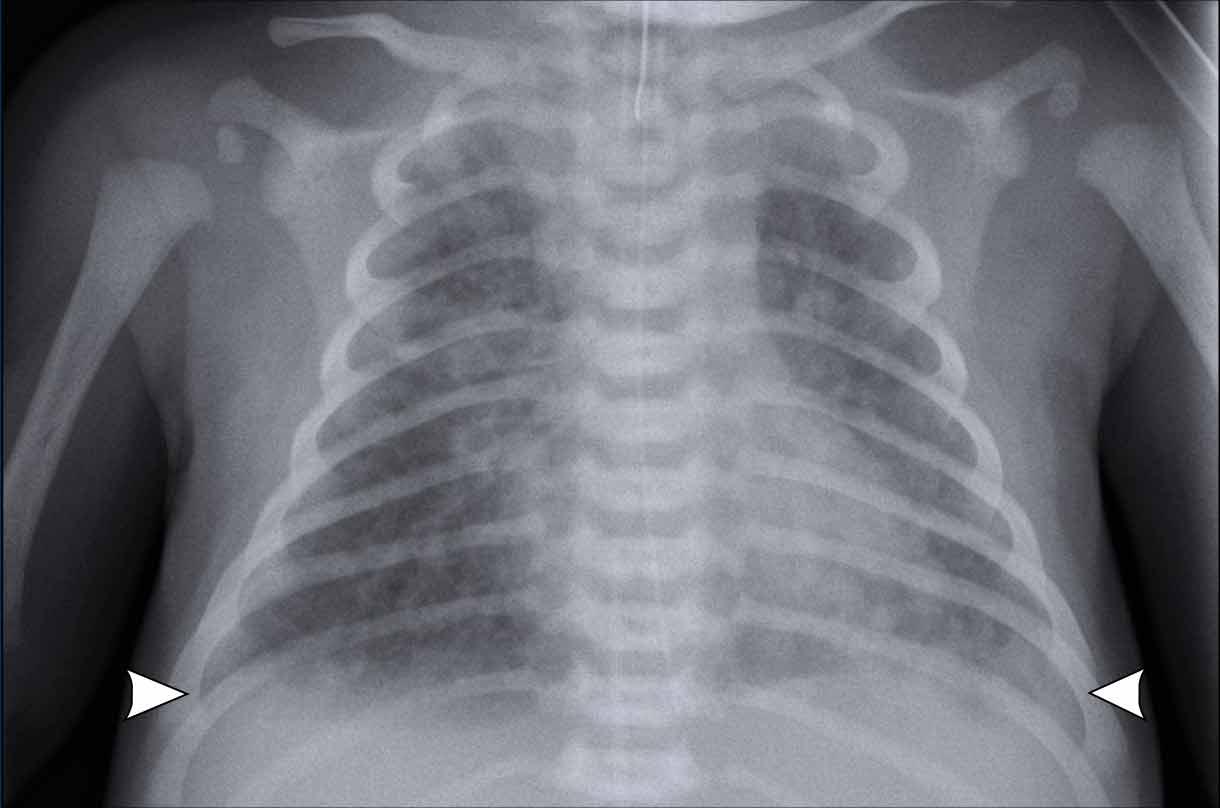

Phim X-quang ngực của trẻ sơ sinh đủ tháng với nước ối nhuộm phân su.

Image

- Hyperinflation

- Course diffuse

patchy consolidations on both sides. - Some subtle

pleural fluid on both sides (arrowheads). - Vị trí tốt

ống NKQ. Ống thông dạ dày vị trí nông, vẫn còn trong thực quản. - Đường tĩnh mạch rốn đặt sâu với đầu catheter nằm trong tâm nhĩ phải.